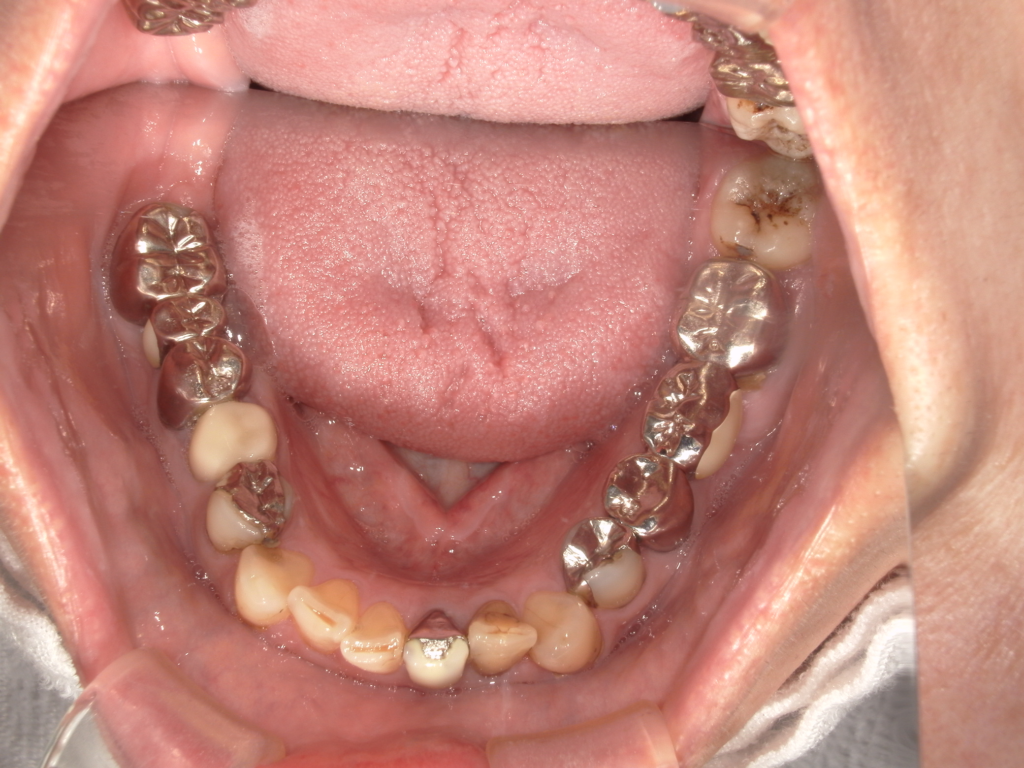

Y様インプラント実例 #44

左の上下の奥歯をインプラントで治療しています。

左下の奥歯は歯を抜くのと同時にインプラントの埋め込みを行っています。

被せものは上下、セラミックスで作っています。

治療前

治療後